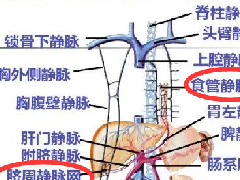

59 岁女性,已婚,无手术史,体格检查完全正常。CA19-9 肿瘤血清标志物和癌胚抗原均为阴性。腹部超声检查显示在胰腺头部有一个圆形病变,回声较低且不均匀。

图 1.1 胰头部肿瘤,呈低回声